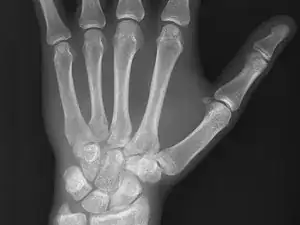

Bildgebende Verfahren sind visuelle Darstellungen von körperinternen Strukturen (unter Haut und Knochen). Diese Bilder kann man dann für klinische Analysen, Diagnosen und Identifikation von nicht normalen Zuständen verwenden, um Behandlungspläne zu erstellen. Bildgebende Verfahren verwenden eine Vielzahl von Technologien basierend auf den Bereichen der Untersuchung inklusive (aber nicht nur) „Röntgen, Magnet-Resonanz-Tomographie, Ultraschall, Endoskopie, Elastografie, taktile Bildgebung, Thermografie, medizinische Fotografie, Technologien, die Kernkraft verwenden wie Positron-Emissions-Tomografie (PET) und Einzelphotonen-Emissions-Computertomografie (SPECT).“